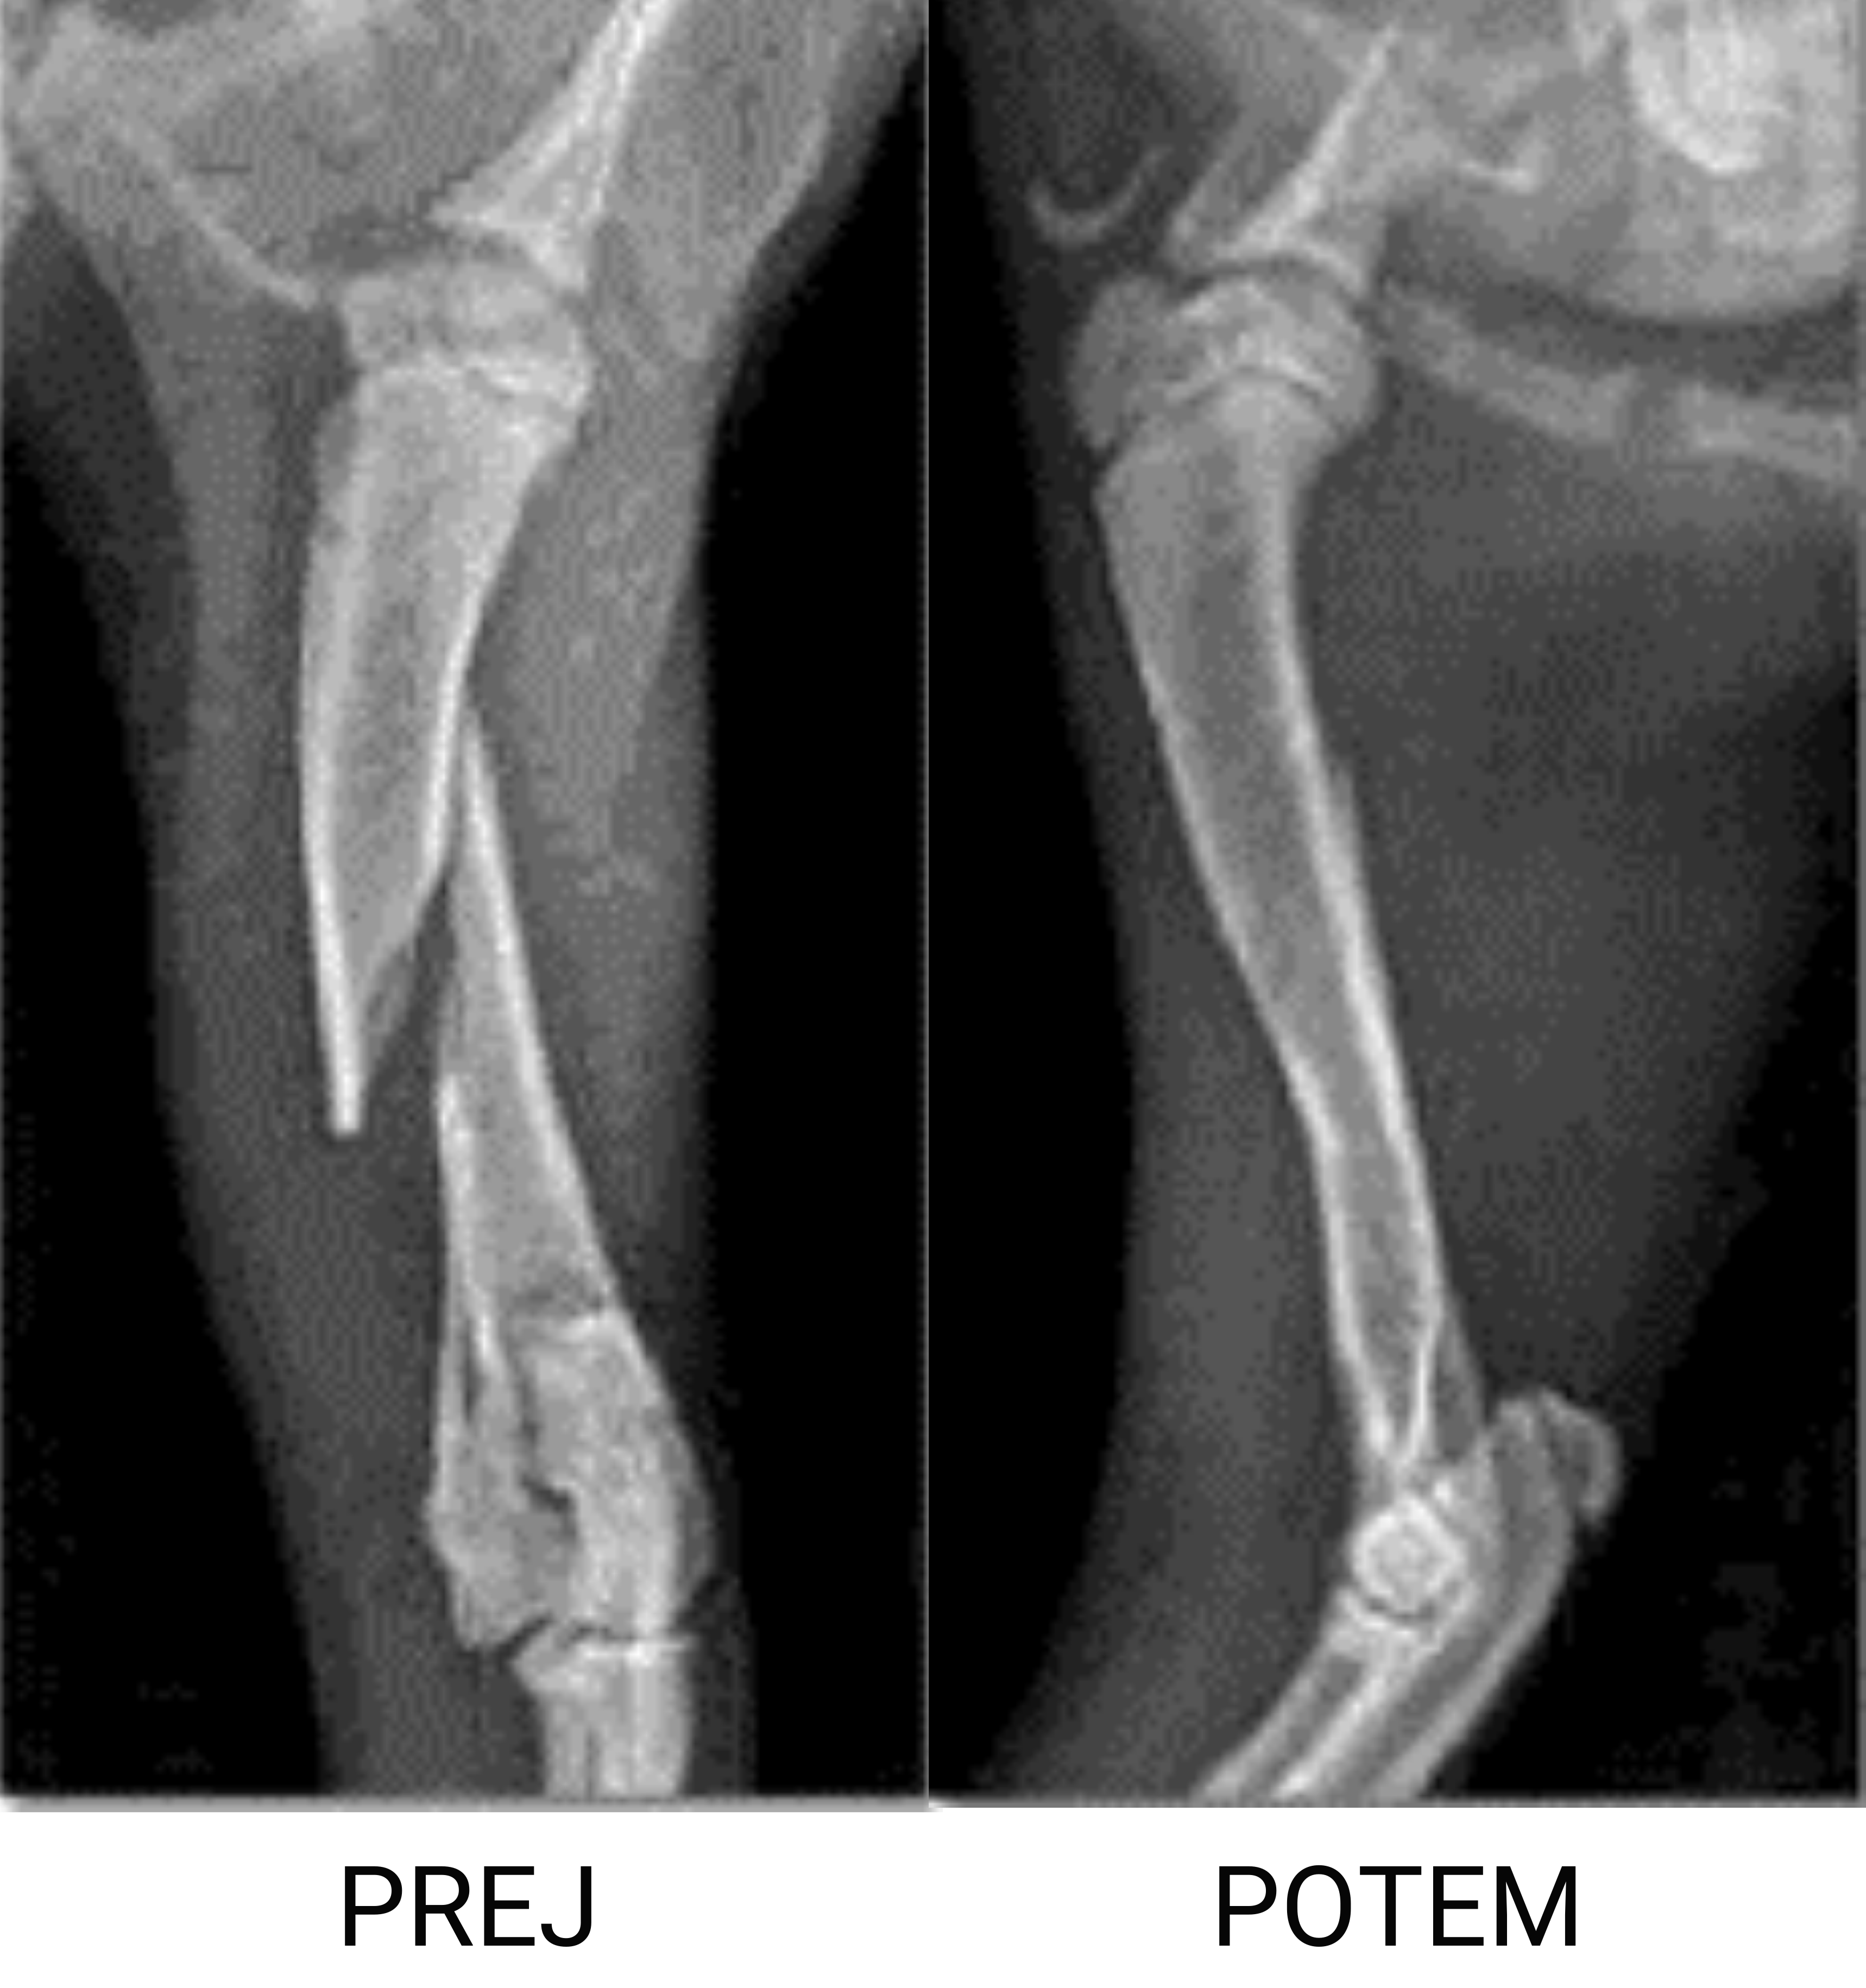

Skrajša čas celjenja zloma.

Že od nekdaj smo mislili, da bi le s skrbnim in stalnim raziskovanjem lahko našli ideje in načrtovali izdelke, ki vplivajo na dobrobit uporabnikov. Raziskovalni laboratorij podjetja PlatiuMed, visoko usposobljena ekipa zdravnikov, inženirjev, fizioterapevtov, trenerjev in oblikovalcev, ki že leta izdelujejo inovativne rešitve za udobje. Skupna sinergija različnih kompetenc omogoča doseganje visokih standardov kakovosti in prestižnih mednarodnih priznanj. Spodaj je nekaj primerov doseženih rezultatov z magnetno terapijo. Rezultati so povprečje testov, opravljenih na vzorcu 100 živali.